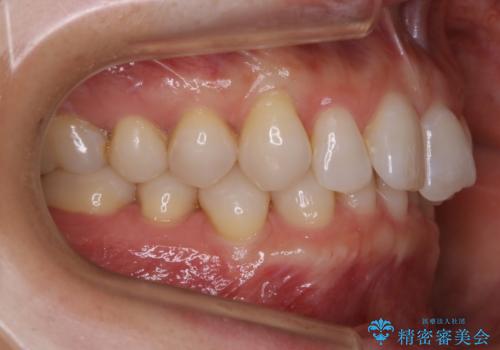

【抜歯】矯正治療とインプラントで正常な噛み合わせを実現

- 30代 女性

- マウスピース(インビザライン)

- 2年2ヶ月

- 元々は矯正治療を主訴にご来院されました。

治療を始めるにあたり、精密検査を受けていただき全体の状況を把握したうえで矯正治療の計画を立てることとなりました。

その過程で左下の6番目の歯は治療が必要な状態であることが分かり、被せ物を外して内部を確認してみると根が破折してしまっていることが判明しました。

歯が深い位置で破折している場合は基本的には抜歯が選択されます。

様々な治療プランを患者さんと相談させて頂き、最終的にインプラントで噛み合わせを回復させていくこととなり、まず悪くなっている歯を抜歯することから開始しました。